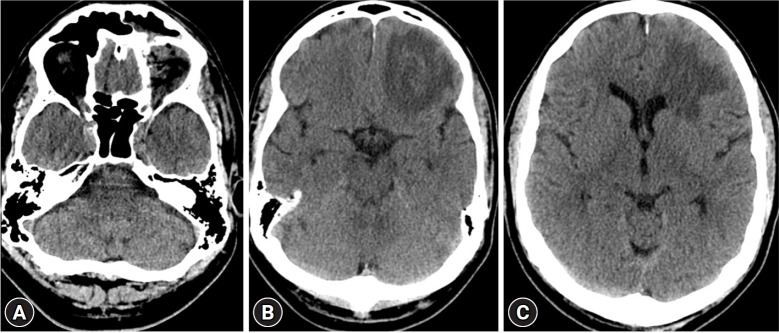

低速眼眶穿透伤可能导致颅内异物滞留,需要手术取出。我们描述了经眶内镜取出额叶内滞留的伞尖的手术,该异物继发于眶顶创伤。这项技术有助于彻底清除异物,而不会对周围组织造成额外损伤。患者术后恢复顺利。我们还讨论了经眶神经内窥镜手术在处理此类外伤时的实用性。

Low-velocity orbital penetrating injuries may result in an intracranial retained foreign body that requires surgical removal. We describe the endoscopic transorbital removal of a retained umbrella tip in the frontal lobe, which was secondary to trauma to the orbital roof. This technique facilitated the complete removal of the foreign body without causing additional damage to the surrounding tissue. The patient had a successful postoperative recovery. We also discuss the utility of the transorbital neuroendoscopic procedure in managing these traumatic injuries.